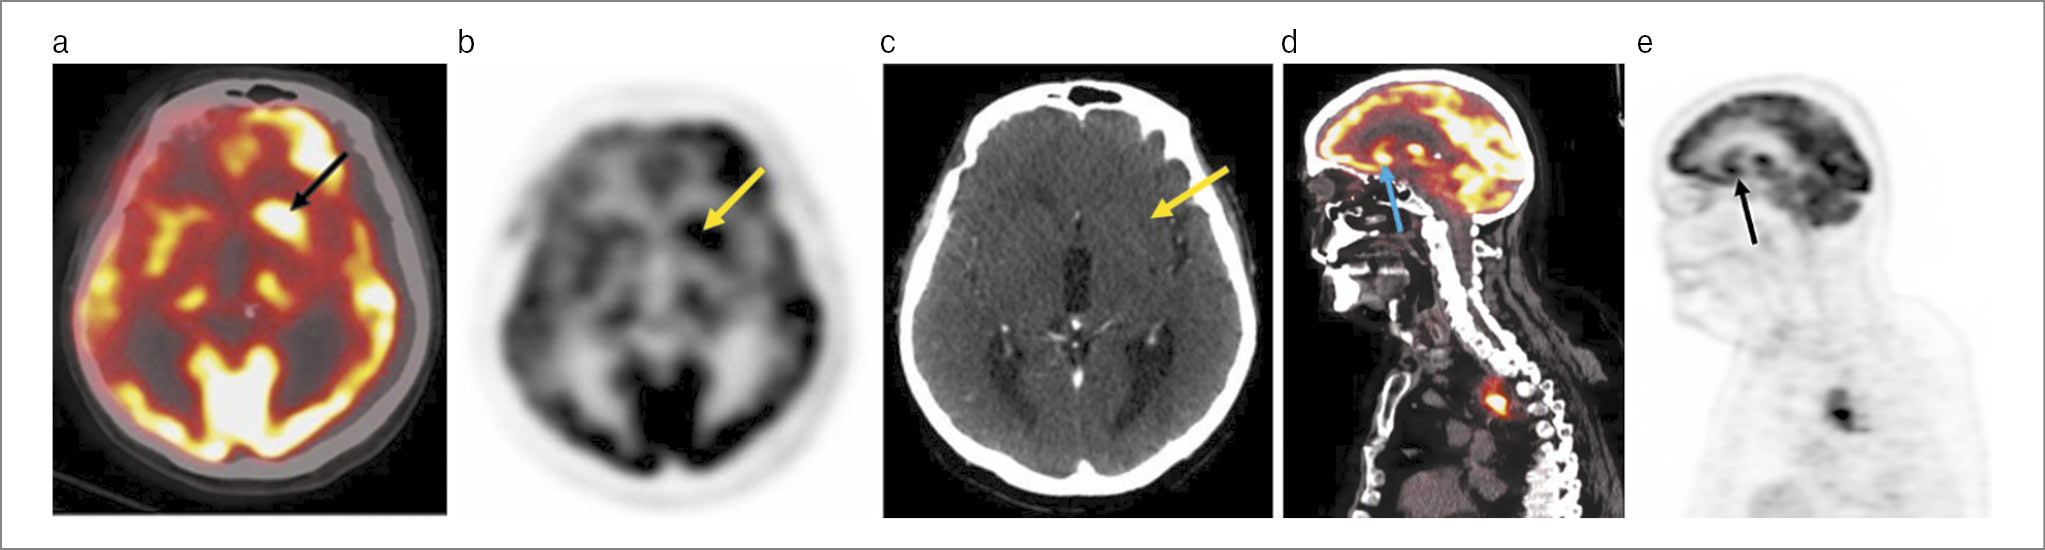

Учитывая отрицательную клиническую динамику и результаты предыдущих методов обследования, с целью подтверждения ранее поставленного диагноза ПЛЭ проведена оценка метаболизма головного мозга и выявление первичного опухолевого очага с помощью ПЭТ/КТ с 18F-ФДГ. По результатам исследования в медиальных отделах левой височной доли отмечается гиперфиксация радиофармпрепарата – РФП (рис. 2).

Рис. 2. Пациент Б., 56 лет. ПЭТ/КТ головного мозга с 18F-ФДГ: a – аксиальная проекция ПЭТ/КТ-исследования; b – аксиальная проекция максимальной интенсивности (MIP); c – аксиальная проекция КТ-исследования; d – сагиттальная проекция ПЭТ/КТ-исследования; e – сагиттальная проекция MIP. Во всех проекциях отмечается гиперфиксация 18F-ФДГ в медиальных отделах левой височной доли размерами 14×18 мм (маркирована стрелками).